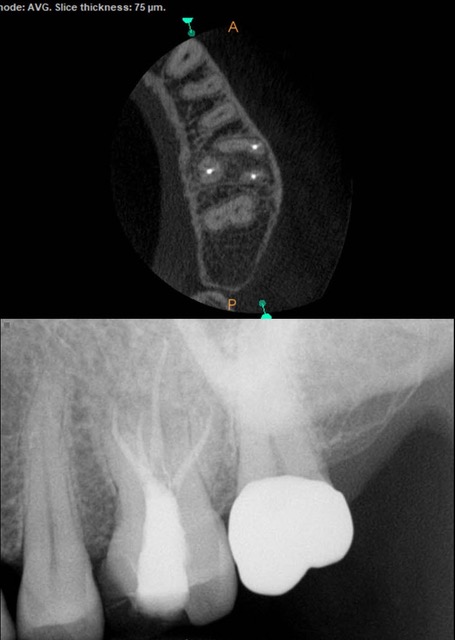

The Procedure of a Root Canal Treatment

To begin, our endodontist will start by numbing the area around the affected tooth using local anesthesia. This ensures that you feel little to no pain during the procedure. Once you are numb and comfortable, our endodontist will create a small access hole in the crown of your tooth. Through this access point, they will carefully remove any infected or damaged pulp from within the roots and chambers of your tooth. This helps eliminate any infection and prevents further damage to surrounding tissues.

After cleaning out all traces of infection, our endodontist will then shape and sterilize the canals before filling them with a rubber-like material called gutta-percha. This material provides stability and prevents reinfection.

In some cases where there is extensive damage or an increased risk of fracture, a dental crown may be recommended for added protection. Our endodontist will take impressions of your teeth to create a customized crown that perfectly fits over your treated tooth.